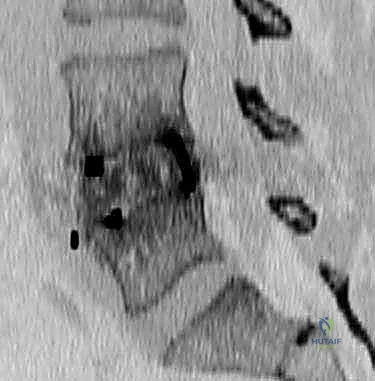

- التصوير بالرنين المغناطيسي (MRI): المعيار الذهبي لتقييم الأنسجة الرخوة. يوضح بدقة حالة الأقراص الفقرية، ودرجة جفافها، ومقدار الضغط على الحبل الشوكي وجذور الأعصاب.

- التصوير المقطعي المحوسب (CT Scan): يقدم تفاصيل دقيقة للغاية عن البنية العظمية، وهو ضروري جداً للتخطيط الجراحي، خاصة في حالات استئصال الجسم الفقري أو وجود تعظم شديد.

الخطوة 2: إزالة العظم والقرص (The Corpectomy)

يتم إزالة الأقراص الفقرية الموجودة أعلى وأسفل الفقرة المصابة. ثم، باستخدام أدوات جراحية متخصصة ومثاقب دقيقة عالية السرعة، يقوم الجراح باستئصال الجسم الفقري التالف تدريجياً. يتم العمل بحذر شديد لإزالة أي شظايا عظمية أو أنسجة ورمية تضغط على الكيس الجافي والحبل الشوكي، حتى يتم تحرير الأعصاب بالكامل (Decompression).